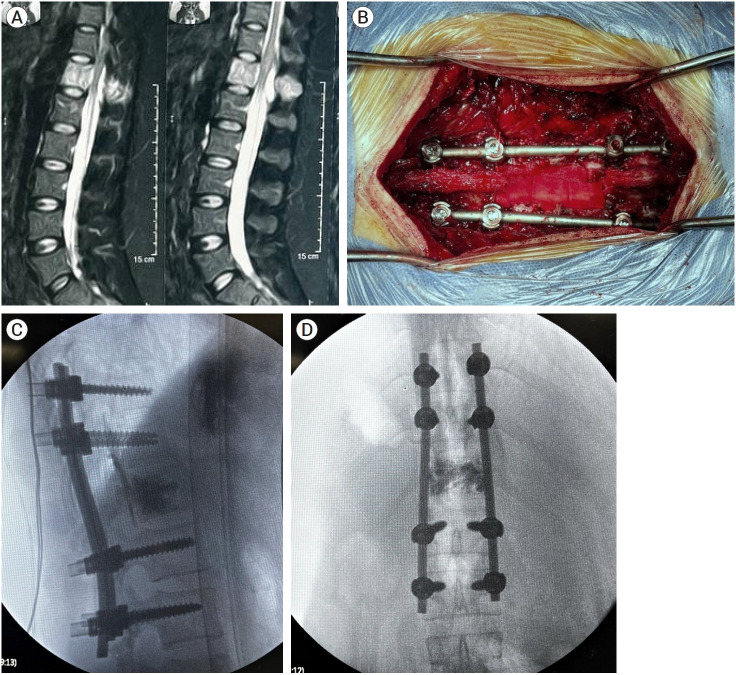

{"title":"Multi-modal management of aggressive vertebral hemangioma: A single center experience.","authors":"Mohamed Farouk, Mohamed Ali Kassem, Ashraf Ezzeldein, Mohamed Mohsen Ameen, Ali Hassan Elmokadem, Mohamed M Elsherbini","doi":"10.7461/jcen.2025.E2024.12.003","DOIUrl":null,"url":null,"abstract":"<p><strong>Objective: </strong>This study aims at spotlighting different lines of management of aggressive vertebral hemangioma (VH) through a retrospective analysis of single center experience.</p><p><strong>Methods: </strong>Patients diagnosed with aggressive VHs in a tertiary referral center were reviewed from 2014 through 2024. Data of patients who met the inclusion criteria were analyzed. Patients of all ages, both sexes, and all varieties of clinical presentation were included, only patients who underwent at least one intervention were included.</p><p><strong>Results: </strong>The study included nine patients, comprising six females and three males, with a mean age of 29.3 years (ranging from 14 to 46). Six patients underwent Trans-arterial embolization (TAE), of whom five underwent further surgical procedures, while one patient found TAE to be sufficient as a stand-alone management technique. Eight patients underwent surgical management, five of whom were pre-operatively embolized.</p><p><strong>Conclusions: </strong>Aggressive VHs are rare, and their management is challenging. Most cases require a multi-modal management, especially when presented with neurological deficit. Pre-operative embolization and/or vertebroplasty are safe and useful tools to decrease intra-operative bleeding of such a vascular pathology in cases undergoing open surgical procedures.</p>","PeriodicalId":94072,"journal":{"name":"Journal of cerebrovascular and endovascular neurosurgery","volume":" ","pages":"40-49"},"PeriodicalIF":0.0000,"publicationDate":"2025-03-01","publicationTypes":"Journal Article","fieldsOfStudy":null,"isOpenAccess":false,"openAccessPdf":"https://www.ncbi.nlm.nih.gov/pmc/articles/PMC11984272/pdf/","citationCount":"0","resultStr":null,"platform":"Semanticscholar","paperid":null,"PeriodicalName":"Journal of cerebrovascular and endovascular neurosurgery","FirstCategoryId":"1085","ListUrlMain":"https://doi.org/10.7461/jcen.2025.E2024.12.003","RegionNum":0,"RegionCategory":null,"ArticlePicture":[],"TitleCN":null,"AbstractTextCN":null,"PMCID":null,"EPubDate":"2025/3/13 0:00:00","PubModel":"Epub","JCR":"","JCRName":"","Score":null,"Total":0}

Results: The study included nine patients, comprising six females and three males, with a mean age of 29.3 years (ranging from 14 to 46). Six patients underwent Trans-arterial embolization (TAE), of whom five underwent further surgical procedures, while one patient found TAE to be sufficient as a stand-alone management technique. Eight patients underwent surgical management, five of whom were pre-operatively embolized.

Conclusions: Aggressive VHs are rare, and their management is challenging. Most cases require a multi-modal management, especially when presented with neurological deficit. Pre-operative embolization and/or vertebroplasty are safe and useful tools to decrease intra-operative bleeding of such a vascular pathology in cases undergoing open surgical procedures.